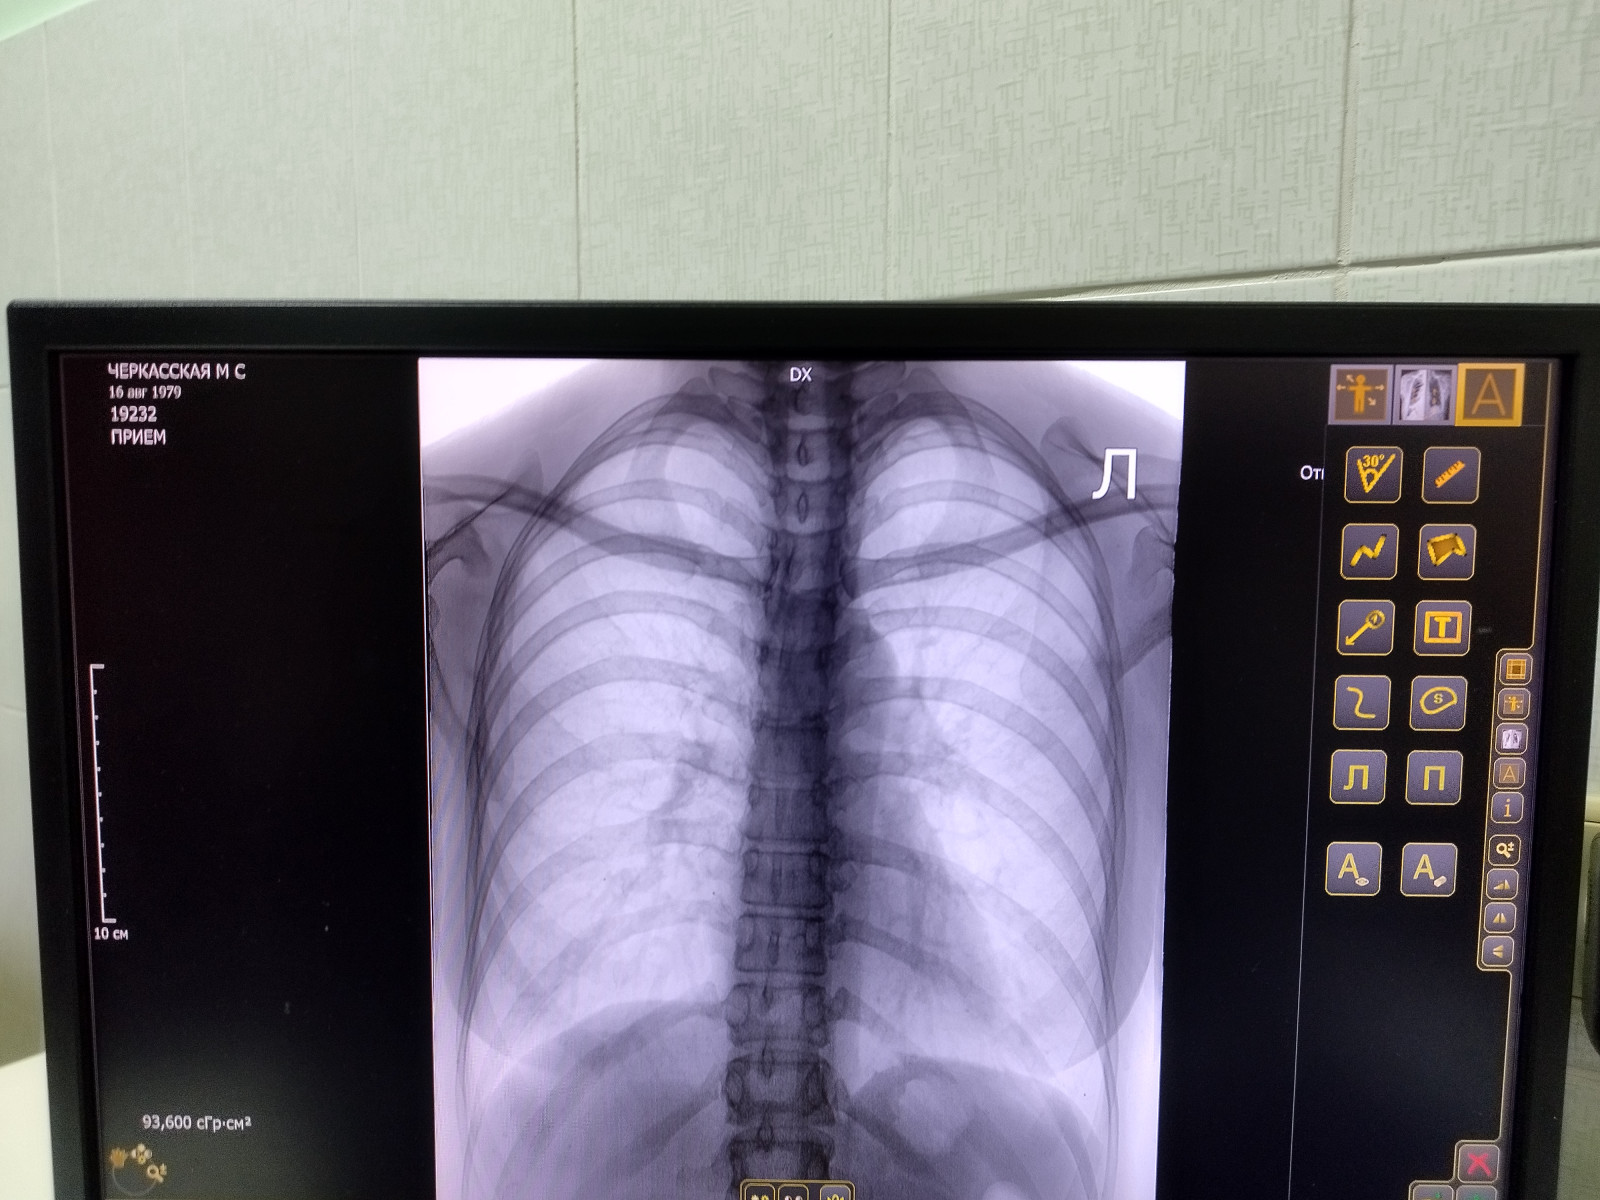

Какой антибиотик пить при определении очаговой инфильтрации в легочном поле слева?